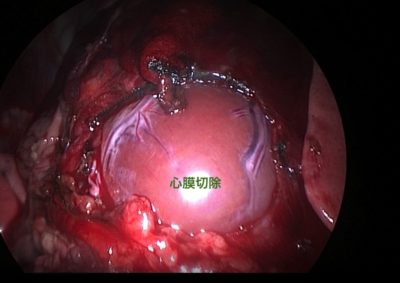

腫瘍外科 注意 ボタンをクリックした先に、治療中および手術中の画像が説明で使用されている場合がございます。 そのような画像に弱い方は閲覧なさらないようお願いいたします。 軟部組織外科腫瘍外科 肺葉切除術 腫瘍外科 胃の腫瘍 軟部組織外科腫瘍外科 大腸腺癌 腫瘍外科 肺葉切除術 腫瘍外科 肝葉切除術 腫瘍外科救急・集中治療 脾臓腫瘤破裂による腹腔内出血 腫瘍外科脳神経科 鼓室に発生した扁平上皮癌 軟部組織外科腫瘍外科救急・集… 脾臓破裂 軟部組織外科腫瘍外科救急・集… 出血性心タンポナーデに対する胸腔鏡下心膜切除術 腫瘍外科 前立腺癌を外科的に切除した犬の1例 腫瘍外科 Mott細胞分化を伴う腸管リンパ腫 Intestinal lymphoma with ... 腫瘍外科 肝細胞癌のチワワの1例 <1234567> 症例カテゴリー 放射線治療整形外科軟部組織外科脳神経外科内科腫瘍外科救急・集中治療リハビリテーション科腫瘍内科内視鏡科脳神経科呼吸器外科中医・漢方猫の腎移植循環器科